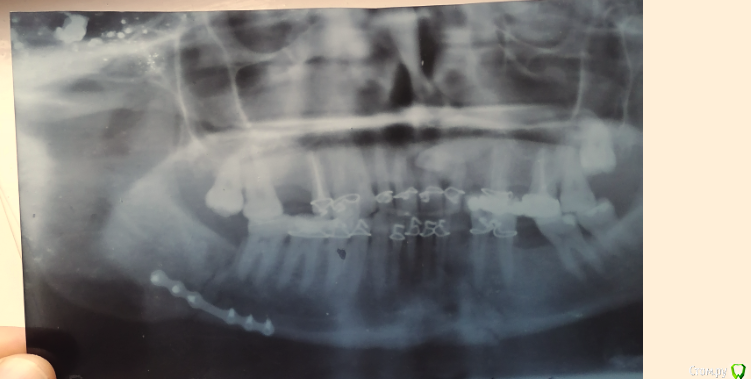

fet1111 Опубликовано 13 ноября, 2020 Поделиться Опубликовано 13 ноября, 2020 Всем здравствуйте!Подскажите пожалуйста,прошло 21 день после шинирование.Сняли крючки и резинки .В двух местах перелом ,с одной стороны поставили пластину.Спереди пластины нету..Я взял и нажал на зуб с переди где перелом соответственно челюсть там где сломано разошлась ..Поехал к доктору и показал что я сделал он наругался на меня и сказал забудь что у тебя там перелом...Все идет по плану...Чувствую что челюсть там где перелом просто давит...Челюсть по новому некто не скреплял..Кушаю роздавливаю еду языком ...После этого всего в целом прошло 32 дня...При откр.. рота я слышу с переди где перелом треск..щелчки..Это нормально?Срастется оно или нет?Как правильно себя вести?Спасибо! Ссылка на комментарий

fet1111 Опубликовано 4 декабря, 2020 Автор Поделиться Опубликовано 4 декабря, 2020 Здравствуйте! Сделал снимок.. Ссылка на комментарий